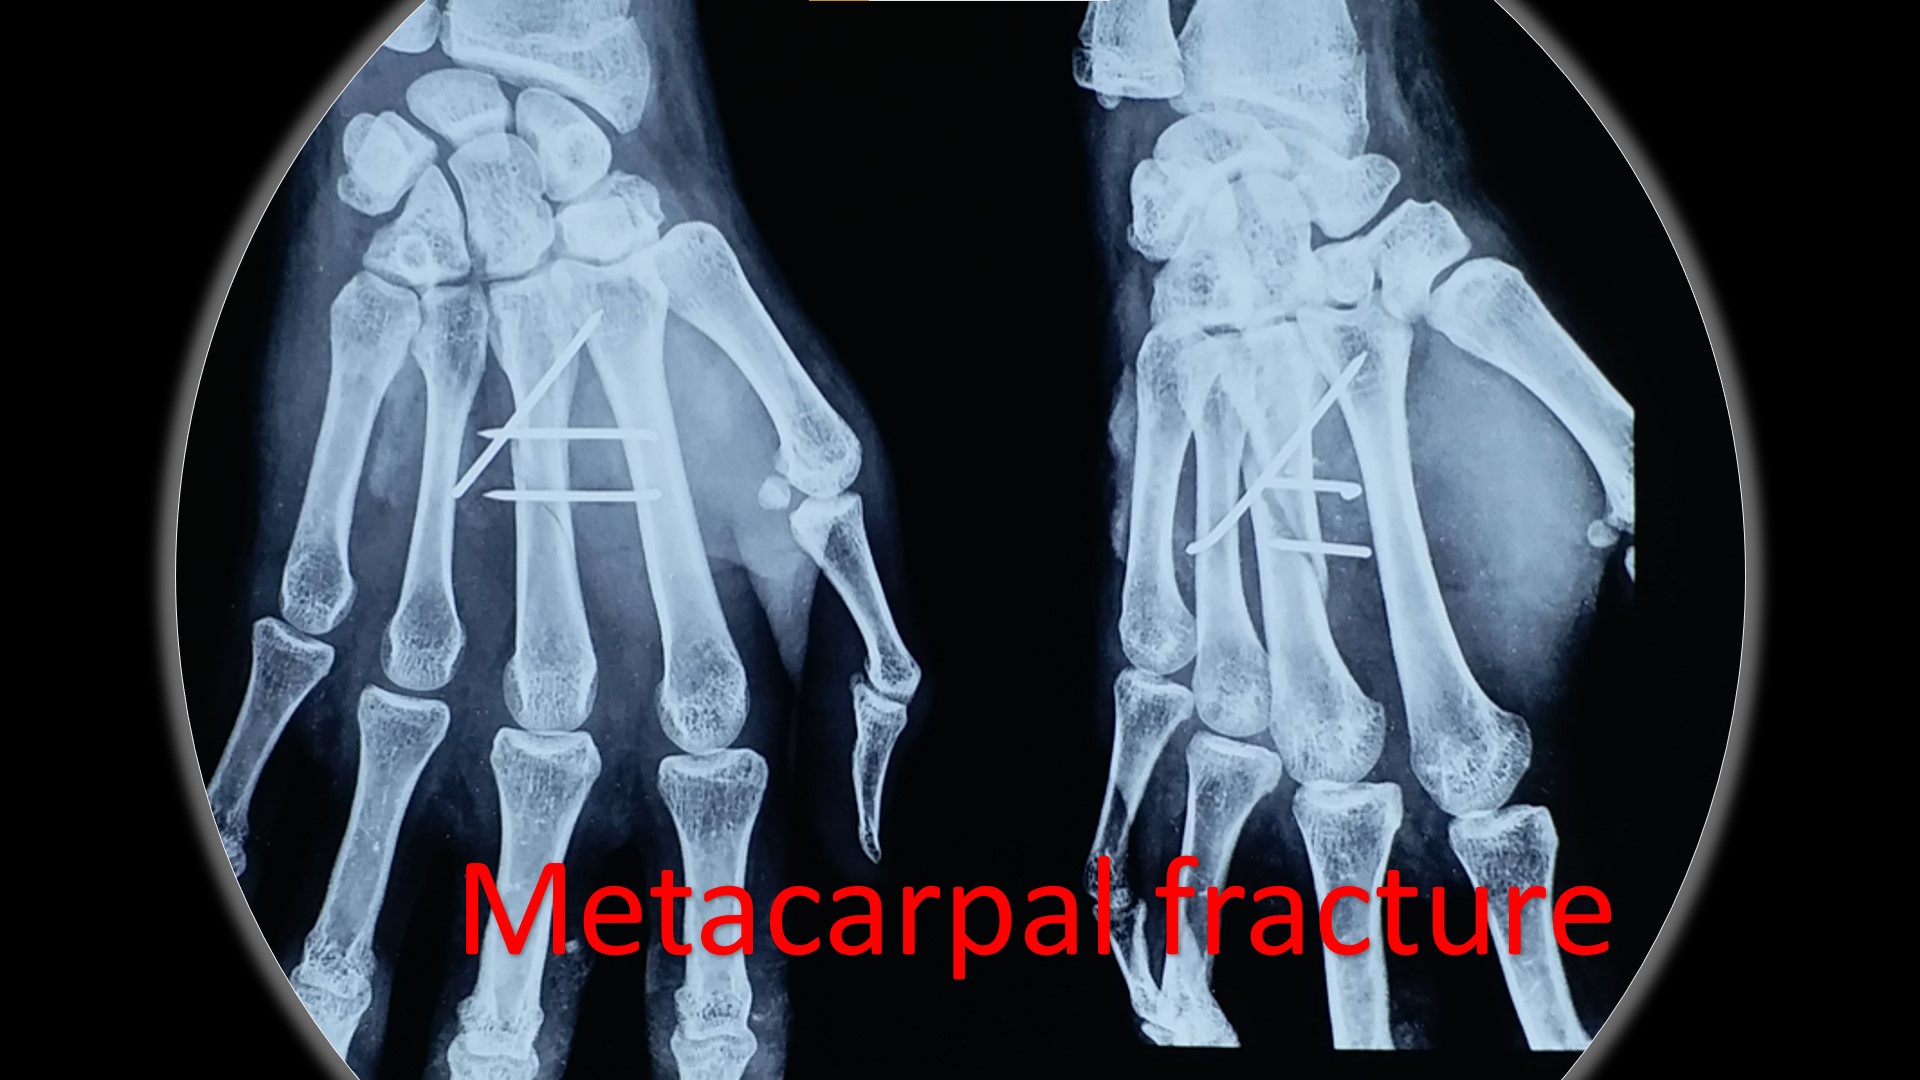

• It can be applied to any intraarticular fractures, distal end radius, elbow, ankle and foot.

• PCCS (Percutaneous Cannulated Cancellous Screws) can be added to CRPP, when interfragmentary compression is a must.

• Early return to some of the personal works like writing, dressing, washing etc from the 2nd postoperative day onwards after CRPP of the fracture distal radius.

• Due to the early implant removal, the functional capacity returns to normal within a short period.